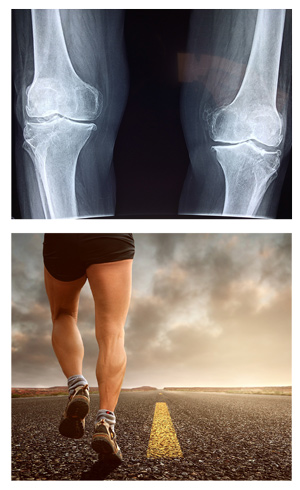

前幾天跑半馬,二十一公里跑完之後,膝蓋的位置好痠好痛,是不是我沒有熱身?雖然以前有舊傷,但兩條腿膝蓋都痛,小腿也好像快抽筋了。」很多上班族都像他一樣,假日跟團去運動,但是平日周一到周五沒有跑步或騎車的習慣,也沒有重量訓練臀部、腿部等肌群,往往每次跑每次痛,痛完再休息一至二周,又繼續比賽,如果持續這樣的循環,很可能摧毀膝關節,直到有一天必須開刀做膝關節置換。小腿快抽筋,是由於長時間跑步,造成的肌肉收縮,導致僵硬和電解質流失而失衡,很多人跑步過程中,感受到緊繃,放任不管繼續跑下去,其實這時就應該到場邊,停下腳步來拉筋,伸展小腿腓腸肌直到疼痛舒緩,並且補充水、電解質減緩。跑步跨步短一點 騎單車雙腳勿外八或內八騎車或跑步後的膝蓋痛,可根據疼痛的位置,分為兩種:一、髂脛束摩擦症候群(ITBS),二、髕骨股骨症候群(PFPS)。髂脛束摩擦症候群痛點是在大腿外側,連接膝蓋外側的位置,因為頻繁的彎曲打直的動作,會讓膝外側的髂脛束變緊,跟大腿外側股骨摩擦久了,就會產生膝蓋外側痛。又或者是因為扁平足、X形腿、長短腳(短的那隻腳),因主力在腿前側、內側肌群,而使得大腿外側髂脛束被拉扯,產生疼痛。如果跑步時,步幅改短一點的跨步,會感覺好一點;騎單車則是要注意,畫圓過程中,雙腳膝蓋和腳尖一同朝著前進方向,而不是外八或內八。賽後或平常日,需要做髂脛束放鬆,可以利用網球,以雙手支撐的側躺姿,運用身體重量,壓在球上,撐開大腿外側的一整條痛點,並訓練較無力的臀部肌群,向後抬腿至腰部高度。或是雙腳外八,膝蓋也朝同方向的外八深蹲,才可以避免過度使用股四頭肌,卻因臀大肌、臀中肌比較弱,都沒使用到而受傷。

髕骨股骨症候群,又稱跳躍膝,痛點是在膝蓋正下方,或膝蓋外側痛為主,「外觀看起來,膝蓋骨(髕骨)好像偏到外面去了,不在正中間。」以走下山坡時,或下樓梯痛感最明顯,醫師指出,好發率估計每五位就有一至二位,而且比較容易發生在女性。因為女生骨盆較寬大,連線膝蓋的Q angle角度過大(股骨,也就是大腿股與脛骨,小腿股之間的角度過大),大腿外側肌群需要更大的力量平衡,造成拮抗肌(對抗收縮肌群的反向肌肉)股內側肌相對弱,造成臏骨偏離軌道,膝蓋不穩定,外翻如火車出軌,髕骨(膝蓋骨)與股骨(大腿骨)之間的摩擦,容易造成股四頭肌腱炎或滑液囊發炎。因此在假日的馬拉松前,平日就該做肌力訓練,訓練較弱的股內側肌群,而不是當假日超人,如果症狀已經造成,貼消炎布並休息,再沒好轉就要看醫生。